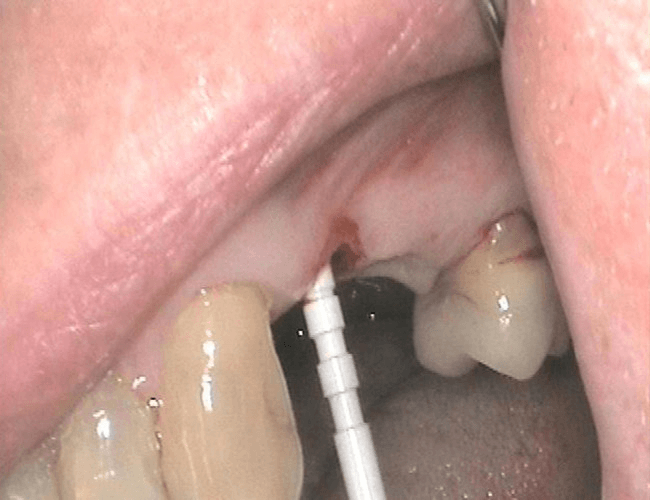

Here are the clinical photos and x-rays of the placement of two zirconia implants. A surgical guide was created after planning using a stone model of the mouth and 3D Conebeam X-ray.